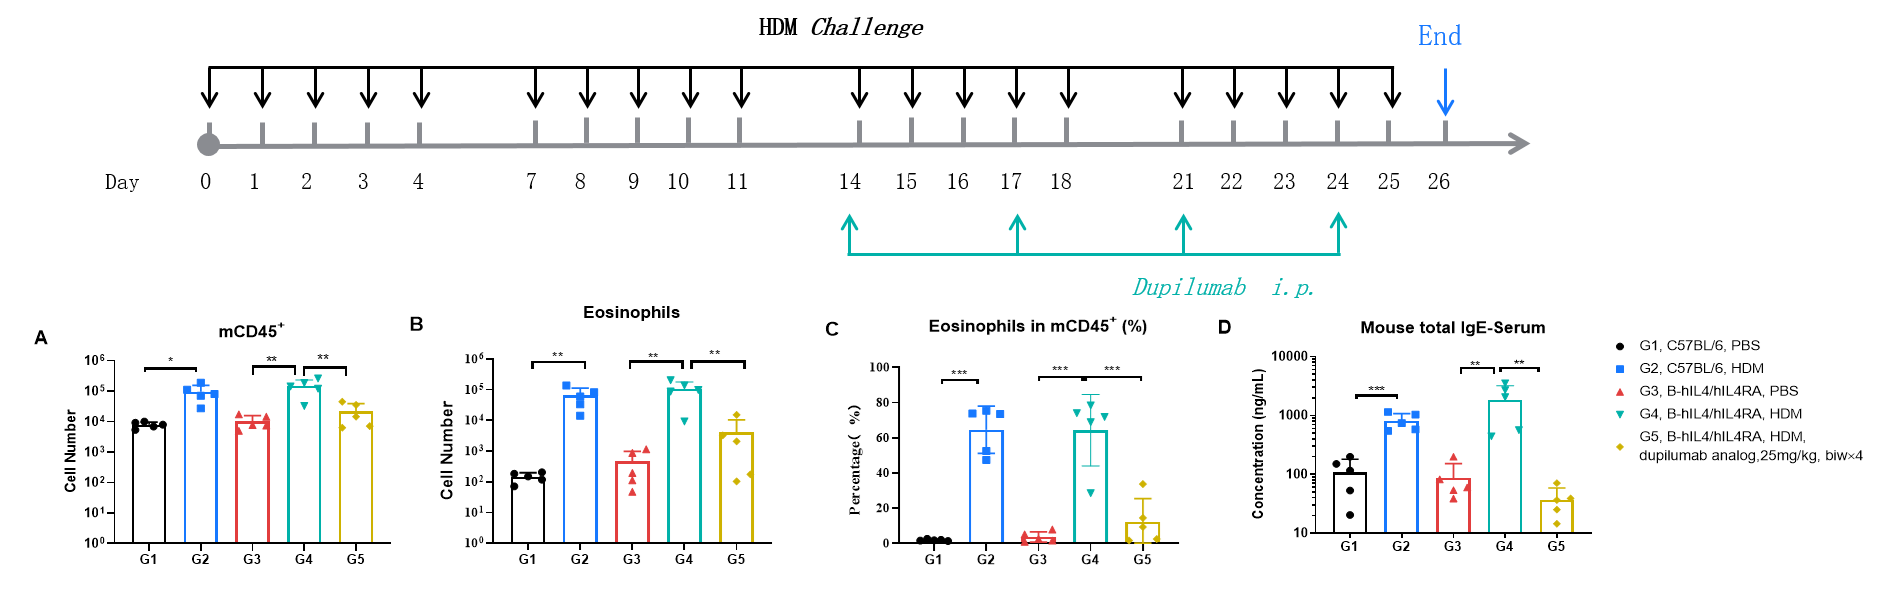

Efficacy Evaluation of the anti-human IL4RA (dupilumab) (in house) in HDM-induced Asthma Model of B-hIL4/hIL4RA mice. (A) The number of CD45+ cells in BALF. (B) The number of eosinophils in BALF. (C) The proportion of eosinophils to CD45+ cells. The results showed that after challenge with HDM, the leukocyte infiltration of mice in G4 model group was significantly increased compared with G3 control group, and their eosinophil content was significantly increased, suggesting that the model was successfully established. After administration of 25 mg/kg dupilumab (in house), the numbers of CD45+ cells and eosinophils were significantly lower compared with the G3 model group. (D) Serum was taken at the end of the experiment and total IgE levels were measured. The results showed that the levels of total IgE in G4 model group were significantly increased compared with G3 control group, suggesting successful modeling. Total IgE levels were significantly lower after administration of dupilumab (in house) drug compared with the G4 model group.

Efficacy Evaluation of the anti-human IL4RA (dupilumab) (in house) in HDM-induced Asthma Model of B-hIL4/hIL4RA mice. ( A) The number of CD45+ cells in BALF. (B) The number of eosinophils in BALF. (C) The proportion of eosinophils to CD45+ cells. The results showed that after sensitization and challenge with HDM, the leukocyte infiltration of mice in G2 model group was significantly increased compared with G1 control group, and their eosinophil content was significantly increased, suggesting that the model was successfully established. After administration of 25 mg/kg dupilumab (in house), the numbers of CD45+ cells and eosinophils were significantly lower compared with the G2 model group. (D) Serum was taken at the end of the experiment and total IgE levels were measured using ELISA. The results showed that the levels of total IgE in G2 model group were significantly increased compared with G1 control group, suggesting successful modeling. Total IgE levels were significantly lower after administration of dupilumab (in house) drug compared with the G2 modeling group. * P?